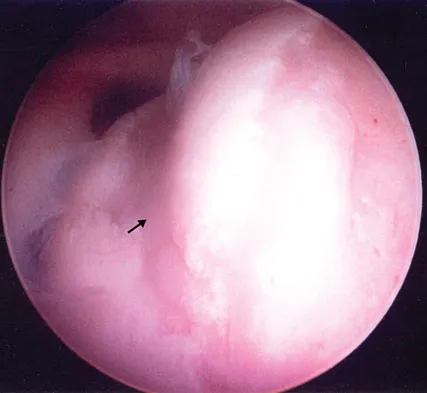

Figure 4a shows the radiograph of a 20-year-old man who has an injury to the right shoulder. Figure 4b shows an arthroscopic view (posterior portal). The arrow points to a

The radiograph shows an anterior dislocation of the shoulder. A frequently encountered sequela of this is a compression fracture of the posterolateral humeral head, commonly referred to as a Hill-Sachs defect. The arthroscopic view of the glenohumeral joint visualizes the posterior aspect of the humeral head. In the image, the area devoid of cartilage to the right is the bare area. The indentation seen to the left is a Hill-Sachs defect. Matsen FA, Thomas SC, Rockwood CA, et al: Glenohumeral instability, in Rockwood CA, Matsen FA (eds): The Shoulder, ed 2. Philadelphia, PA, WB Saunders, 1998, pp 611-754.